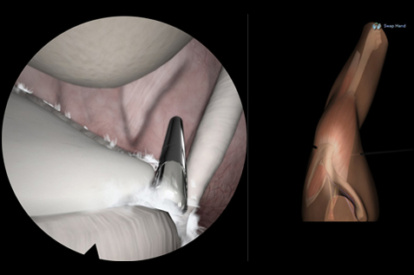

ARTHRO Mentor is an effective tool for arthroscopic surgery skills acquisition. With over 15 years of validation studies, it offers a line of simulated procedures, covering the 3 major joints (shoulder, knee, and hip) combining physical anatomical models with 3D images and dynamic haptic sensation, to allow users to learn key aspects of the procedures while providing tissue sensation.

- Interchangeable knee, shoulder and hip models

This comparative cross-sectional study contrasts the automated performance reports for novice and expert orthopedic surgeons after executing surgical tasks on the ARTHRO Mentor virtual reality simulator. Setting Surgical simulation center at the University of Chile Clinical Hospital, Santiago, Chile. ARTHRO Mentor simulator for knee arthroscopy showed good construct validity, with performance metrics accurately discriminating between expert and novice users.

The results of this study demonstrate learning curves for a hip arthroscopy simulator, with significant improvements seen after three sessions. All performance metrics were found to improved, demonstrating sufcient visuo-haptic consistency within the virtual environment, enabling individuals to develop basic arthroscopic skills.